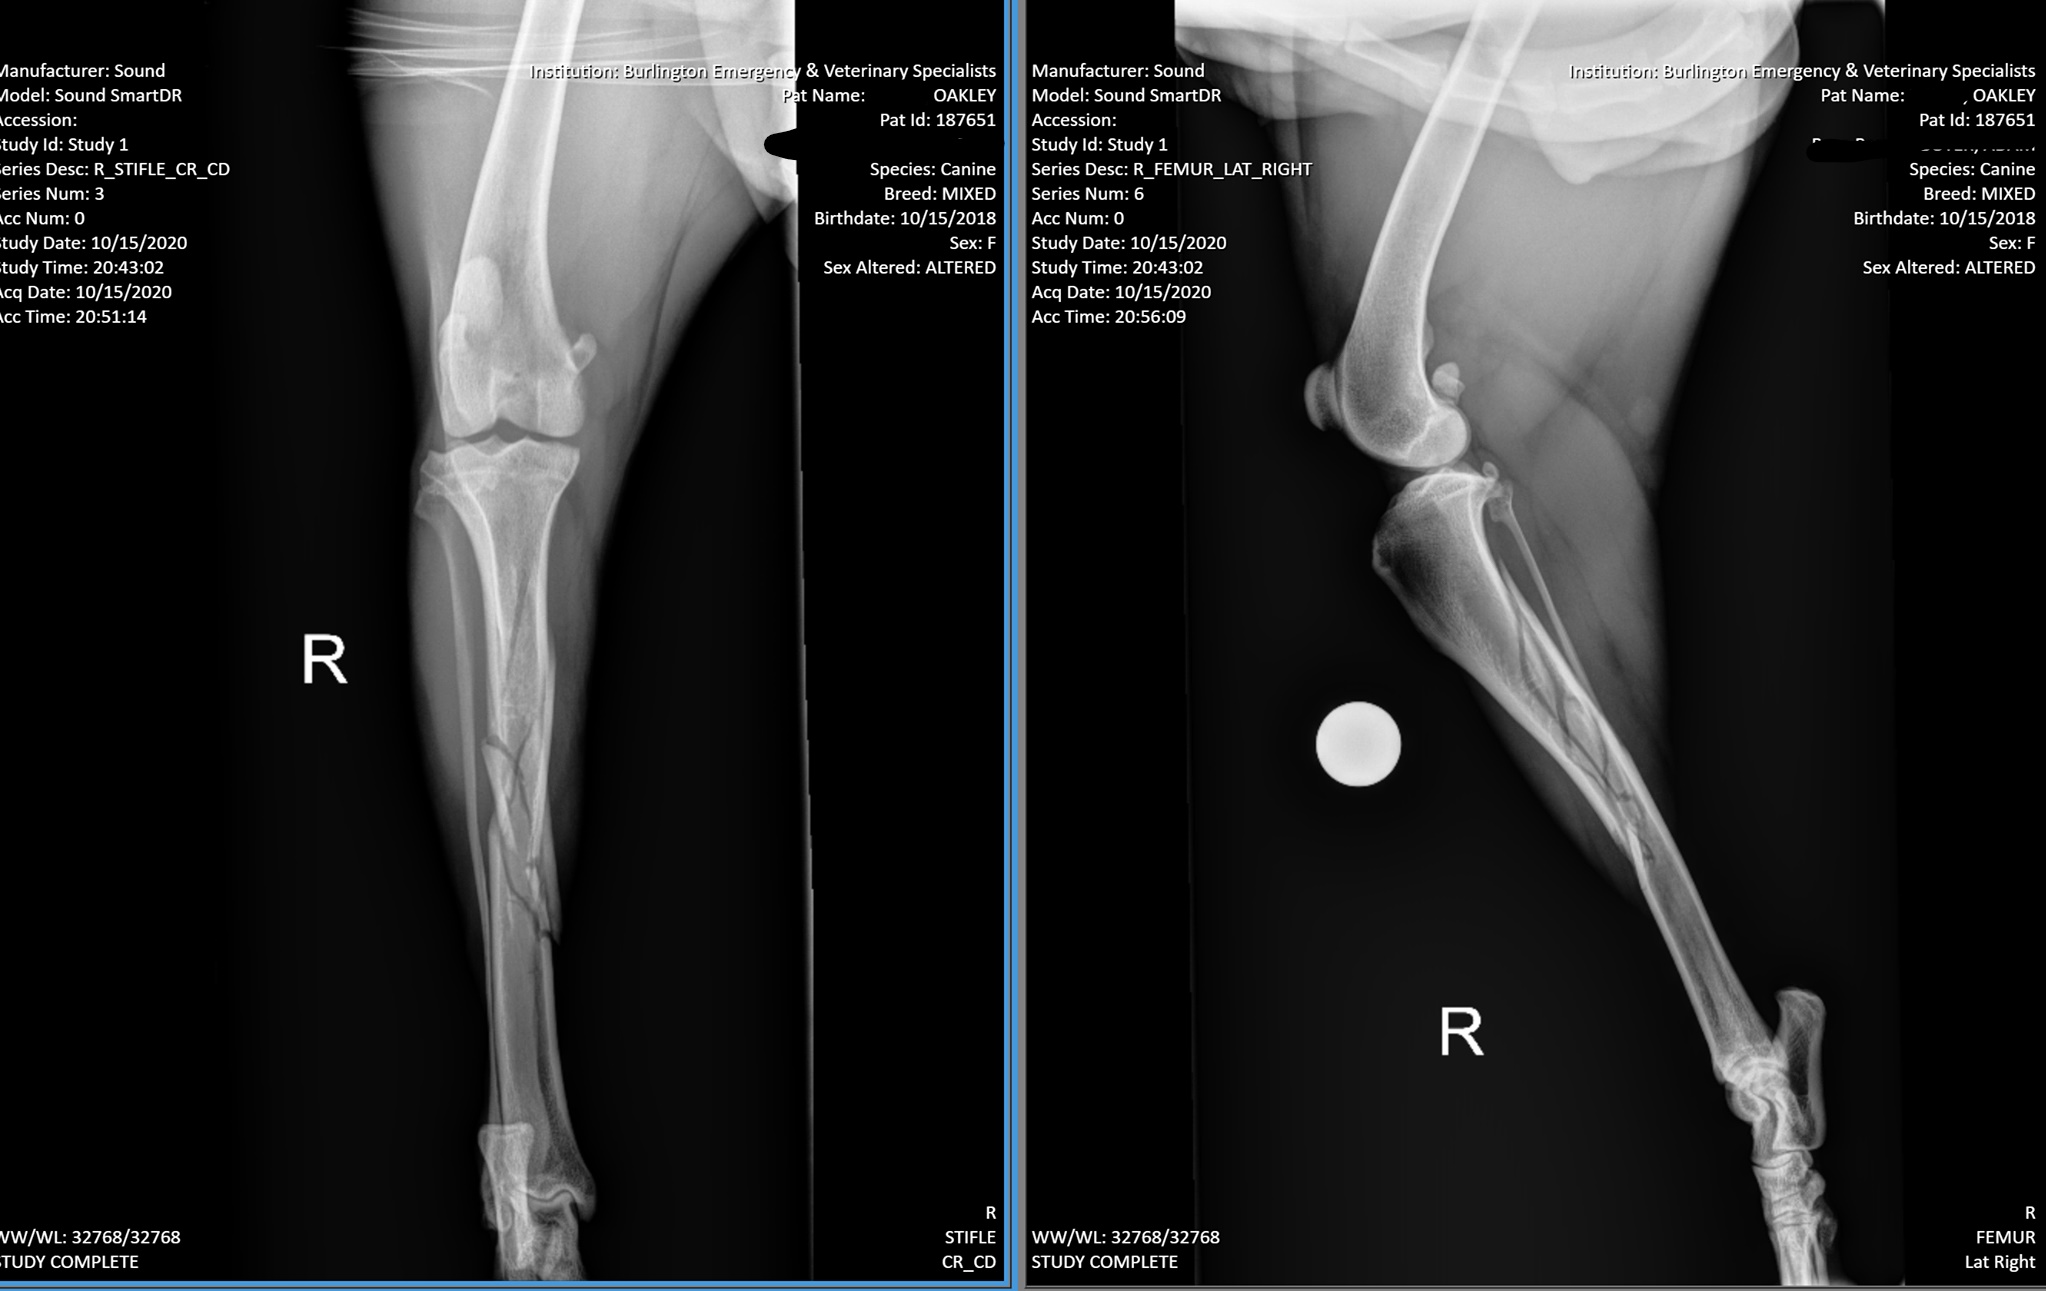

Oakley is a young Walker coon hound that had her leg injured when she was out in the pasture with her family early evening on October 15th 2020. Oakley was brought to the emergency Vet to get check out, she stayed over night to get monitored as she had air & fluid in her chest cavity due to the trauma. She has several fractures in her Tibia. Oakley is needing to have surgery on her right leg. Surgery is not cheap and there will also be follow up visits that will be needing. We are asking for your help!